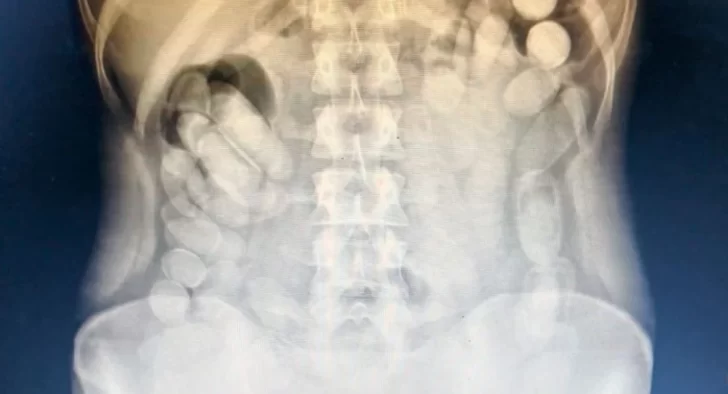

Considerando la situación como un posible caso bajo la modalidad conocida como “capsulero”, y teniendo en cuenta los riesgos para la salud de la involucrada, el Juzgado Federal Nº 2 ordenó su traslado al hospital Centro de Salud en la capital de la provincia de Tucumán. Allí, mediante una radiografía, se confirmó la presencia de las cápsulas en el abdomen de la mujer. Posteriormente, la misma evacuó un total de 106 cápsulas.